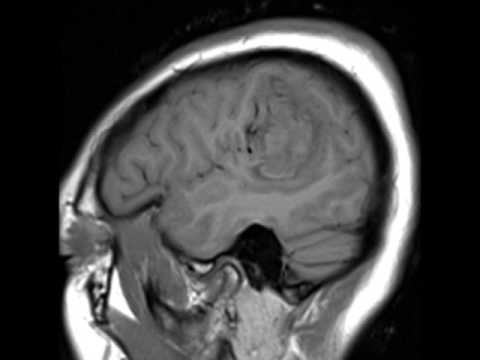

Hellow guys, Welcome to my website, and you are watching Nav-guided transsylvian approach & microsurgical resection of a deep left temporal low-grade AVM. and this vIdeo is uploaded by American Association of Neurological Surgeons at 2017-08-10T14:21:52-07:00. We are pramote this video only for entertainment and educational perpose only. So, I hop you like our website.